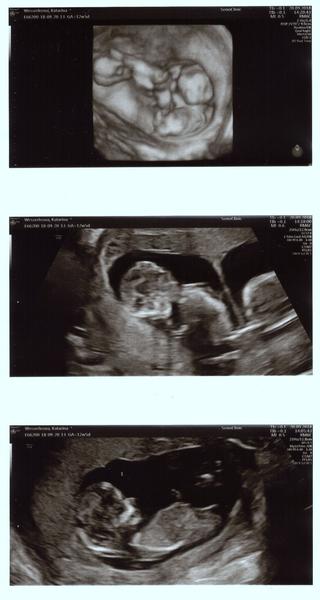

Ahojte baby, tak dnešný ultrazvuk dopadol dobre, všetko je v poriadku, doktorka pomerala všetko a detičky vyzerajú zdravé, zobrali krvičku a výsledok bude o týždeň, objednala som sa už aj v 20tt na morfologický. Detičky krásne podrástli, hýbali sa o sto šesť, manžel bol nadšený a na 80% to vyzerá na dievčatká.

1 obrázok sú obidve spolu, 2 obrázok jedno bábätko a 3 obrázok druhé bábätko

@babikadaska presne tak sme to videli na utz ako je na prvom

@katka8817 aha tak to som este nikdy nevidela ani netusila ako to vyzera :D wau 🙂 dve baby 🙂